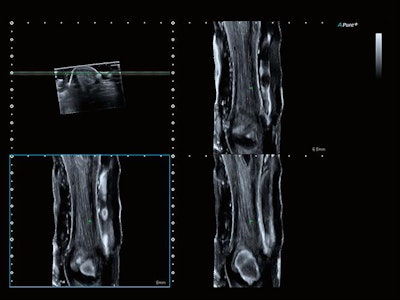

The company's Aplio i800 now features a 33-MHz linear-array transducer that is designed to offer better spatial resolution below 50 microns and improved resolution and detail for B-mode and color flow imaging. Its Smart Sensor 3D allows users to take 3D volumes with a standard linear or convex transducer. The system is particularly suitable for superficial subcutaneous imaging and examinations of small joints and superficial nerves, as well as for superficial vascular evaluations.

Image of Achilles tendon. Coronal view acquired on the Aplio i800 system with Smart 3D at 24 MHz. Image courtesy of Canon.Canon is also showcasing its Xario G series, Xario 200G and Xario 100G, which offer up to eight hours of battery-powered, cordless function, allowing the equipment to be used across a variety of locations in a hospital or clinic.